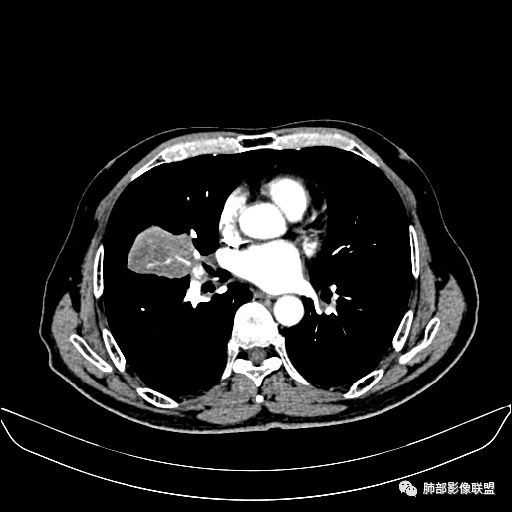

住院4天后行胸部增强CT

动脉期

静脉期

老年男性,因“咳嗽咳痰1月余。”入院。病程中咳嗽咳痰,咳黄白痰,间断咯少许鲜红色痰血。PPD阳性。胸CT:右肺中叶外侧段支气管管腔阻塞,大片实性病变,病灶边缘光滑,部分边缘膨隆,可见分叶,肺门及纵隔可见肿大淋巴结,并可见钙化。增强可见病灶明显强化,而且延迟强化明显,病灶内多发低密度区,内见血管影,血管变细、部分血管破坏。考虑恶性病变可能性大,鉴别慢性肉芽肿性病变。

胸CT:跨叶大肿块,主体在中叶,右中叶外侧段支气管阻塞,病灶部分边缘膨隆,可见分叶,部分边缘平直,肺门及纵隔可见肿大淋巴结。增强病灶不均匀强化,延迟强化明显,病灶内多发低密度区,内见血管飘浮,部分血管变细、模糊。考虑:恶性病变可能性大,大细胞?淋巴瘤?鉴别慢性肉芽肿性病变。

右肺中叶软组织肿块,外围向内生长,叶间胸膜向前内移位,肿块近肺门侧跨叶,中叶外侧段支气管截断,密度不均匀,双侧肺门及隆突下见肿大淋巴结,增强后呈中度不均质强化,肺动脉供血,多发坏死区,边界尚清,坏死区域内见结构,结合病史考虑恶性,鉴别诊断1结核,爬行征是沿支气管树分布,外宽,内窄,周围有卫星灶,内气管狭窄后扩张,此例沿叶间胸膜长轴分布,气管有截断,不典型。2炎性肉芽肿,符合的地方下方层面增强后延迟性轻度环形强化,不符临床无发热等急性感染病史,实验室指标不符,病灶周围渗出及慢性炎性改变有,不明显。

吴婧老师和南边老师都对该病例进行了深入分析。从支气管管壁的增厚,支气管狭窄后扩张,支气管粘液栓,病灶形态,到病灶不均匀强化及坏死彻底,到周边病灶及肺组织空气的潴留,加之纵隔内淋巴结肿大伴钙化等等,都支持慢性炎性病灶,尤其是结核。

墨西哥仙人掌征---结核        影像上结核灶,粗大的均匀枝干,推测是支气管囊状扩张引起的,在非支气管区,形成圆形坏死囊群;如果这些坏死比较稀薄,又遇到扩张支气管,就会形成粗大的“墨西哥仙人掌”。结核引起的支气管近端炎症纤维化,可以造成支气管阻塞,从而将干酪样坏死物封堵在管腔内。仙人掌主干内部应该是干酪为主,稀薄的,具有流动性,时间久了会出现钙化。

结核坏死与鳞癌鉴别有一点是结核坏死没有方向性,鳞癌有。鳞癌靠近支气管近端部分,血供容易维持,不易坏死,所以坏死靠外侧。而结核干酪样坏死,把一定体积的流动性坏死物,包裹起来,什么形状最省料?坏死物包裹,表面积最省的自然是圆球形,而遇到支气管,坏死物一多,就把支气管撑大了。包裹物是就地取材,扩张的支气管就成了包裹结构。